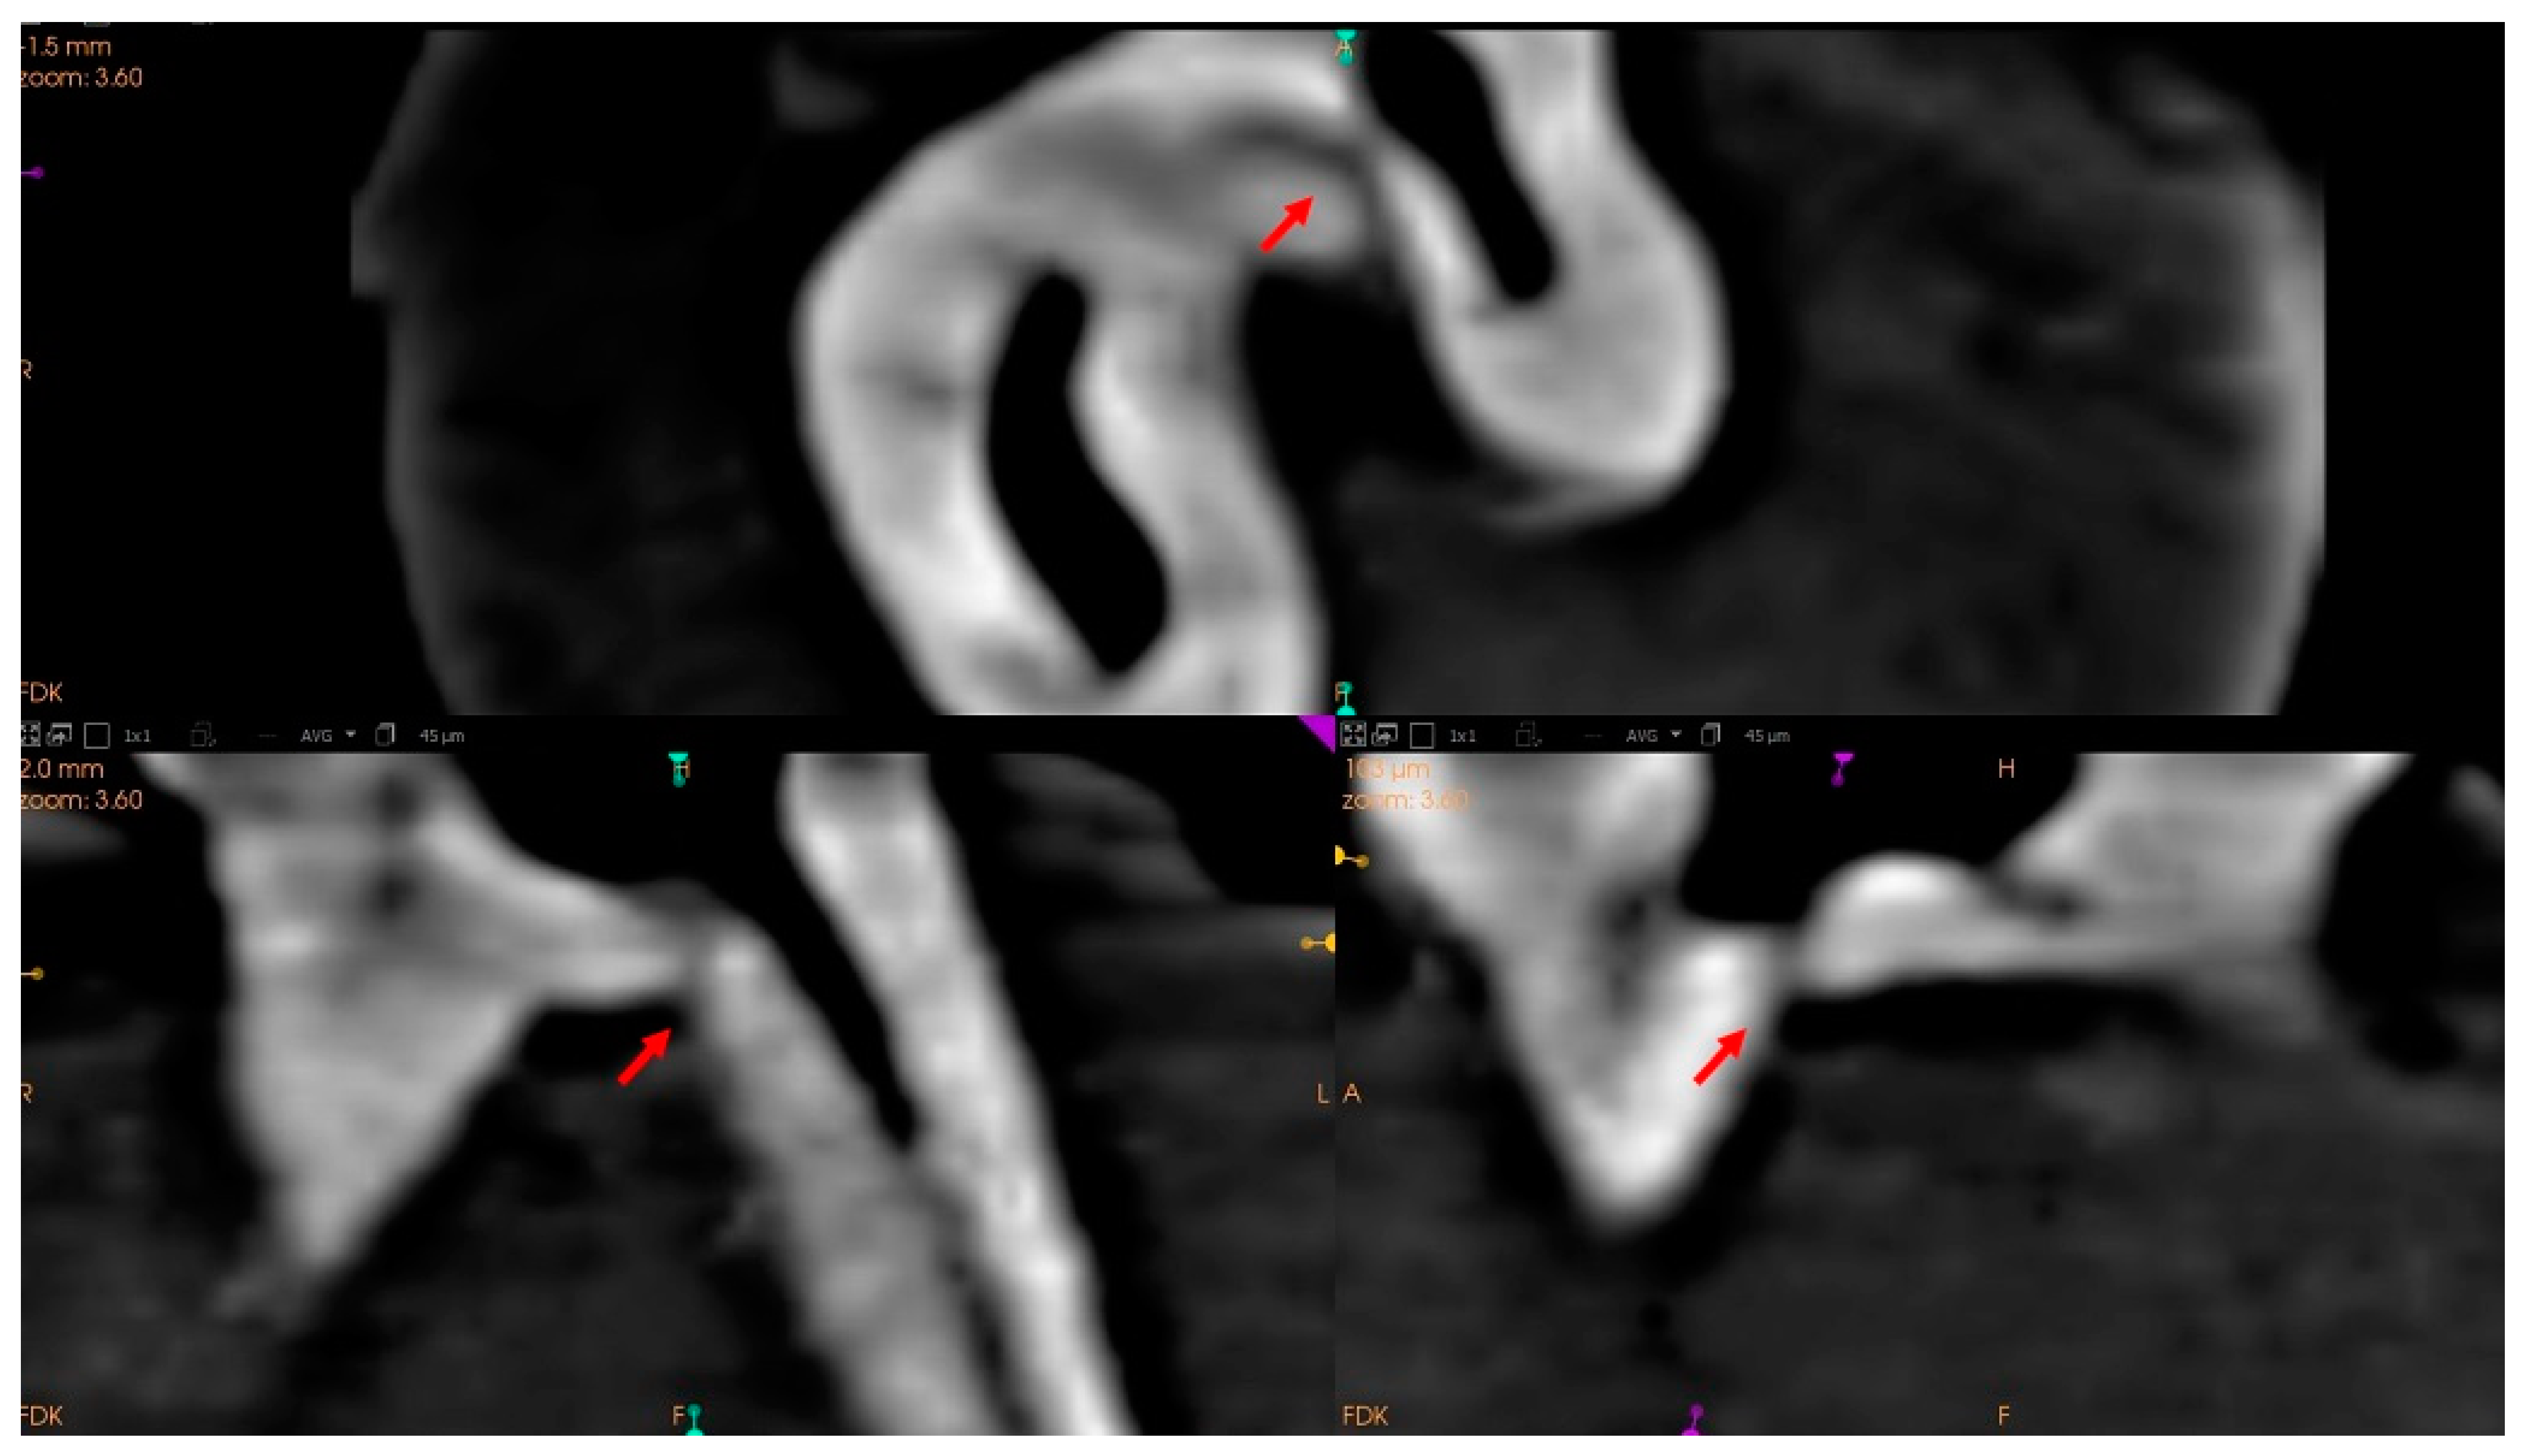

2.4.4. Other Peculiarities